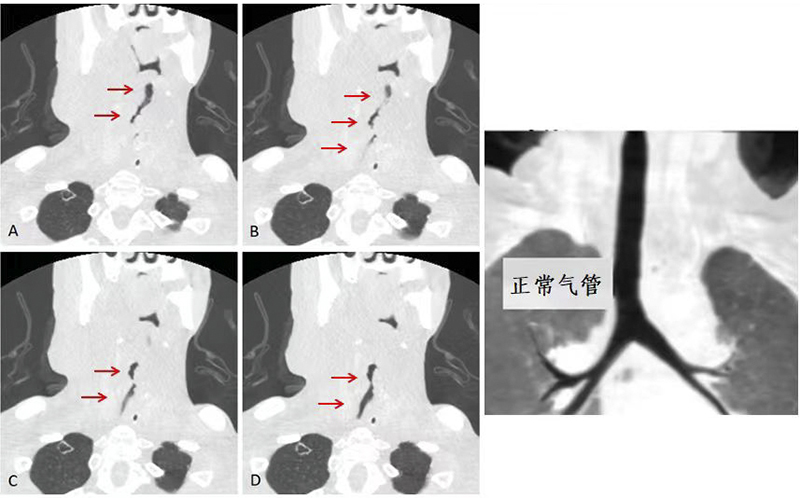

入院完善頸部CT后提示喉癌術(shù)后復(fù)發(fā)及綜合治療后改變,腫物較前增大,合并感染。同時(shí)局部腫瘤侵犯氣管,目前梗阻的氣道隨時(shí)可能危及患者生命,立即建立人工氣道才有可能緩解呼吸困難、挽救生命并且提高患者的生存質(zhì)量。但患者目前的基礎(chǔ)狀況要經(jīng)歷麻醉、建立人工氣道手術(shù),將可能出現(xiàn)插管困難、氣道出血、甚至突發(fā)心臟驟停等情況。面對(duì)患者復(fù)雜的病情及棘手的治療,患者及家屬仍然表達(dá)了強(qiáng)烈的生存意愿,希望盡量延長(zhǎng)生命,并且能最大程度地提高患者的生存質(zhì)量。